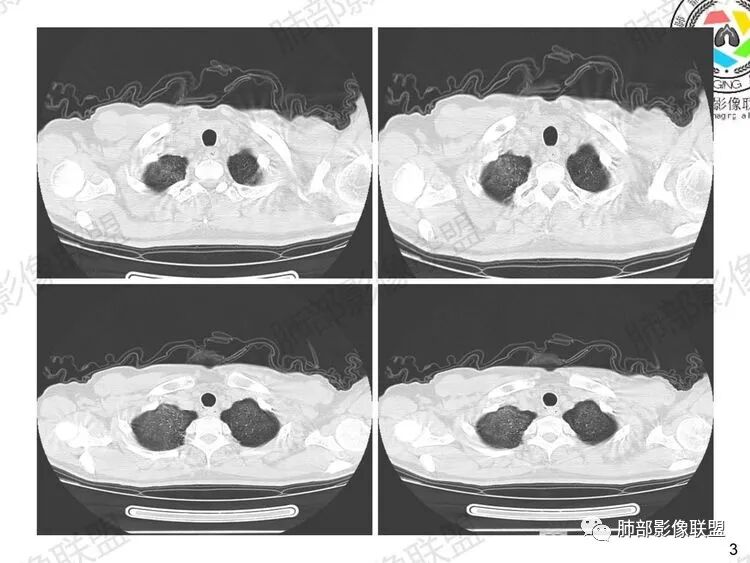

早期:孢子菌滋养体吸入附在肺泡壁上,破坏I型肺泡上皮细胞的细胞膜,使细胞坏死及毛细血管通透性增加。液体渗出到肺泡腔内,病灶主要位于肺泡内,肺泡腔密度增高,间质这时受累相对轻,因此早期为渗出期,病变由中心向外周分布,表现为两肺多发对称性的弥漫斑点状、粟粒状阴影,边界清楚。

中期:孢子菌在肺泡腔内大量繁殖,引起炎性渗出及肺泡上皮增生,肺泡液内含有滋养体的嗜酸性渗出物及纤维蛋白和脱落的上皮细胞,Ⅱ型肺泡上皮细胞增殖修复受损的肺泡毛细血管间膜,肺间质内巨噬细胞、浆细胞和淋巴细胞增殖导致间质性肺炎,就是说有肺泡腔的密度增高,也有间质的增厚,整个肺受累区域密度都增高,形成以肺门为中心双侧对称的弥漫性磨玻璃样改变,胸膜下较少累及,呈典型的月弓征,采用积极的对症治疗后,大多数病变可吸收消失。

1、双肺从中心向外周对称性弥漫分布的磨玻璃密度影,无重力分布特点

2、中内带分布为主,胸膜下较少受累,可见月弓征